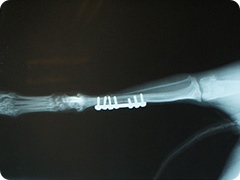

- 骨折

- 高いところから飛び降りたりすることで骨折することがあります。骨折した足はぶらーんとして床に足を付けられない状態になります。

創外固定法による治療

プレートを用いた治療